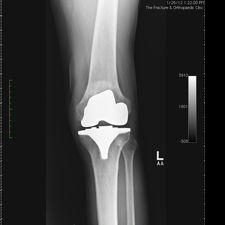

On clinical and radiological examination, he was assessed as having Severe Primary Osteoarthritis of both knees.

Bilateral Total Knee Replacement was recommended, and performed on July 27th 2011. Since surgery, the patient has made good progress and can now mobilize with the aid of a walker.

His x-rays and clinical examination suggest good early outcome with a fully mobilized patient with pain free knees and the ability to walk independently.